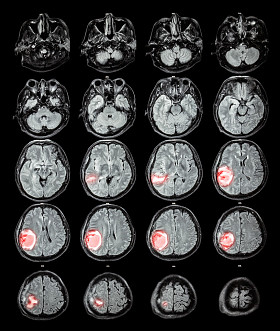

磁共振脑: 显示大脑右顶叶脑肿瘤

图司机为设计师提供高清磁共振脑: 显示大脑右顶叶脑肿瘤图片版权下载,图片为科学技术,大小为4.35MB,尺寸为3407 x 3407px,更多关于图像,蓝色,背景,隔离,リボンとユーロ,人类,人,健康,头,医学,保健服务,医疗,文家,黑色,猫,博士,医院,病人,治疗,疾病,显示,癌症,电影,雷,权利,生病,在,头骨,大众,为,的,诊断,解剖,大腦,x 光,手术,扫描,放射学,X 射线,颅骨,神经病学,肿瘤,叶,磁共振成像,大脑,麻痹,ct,神经外科,顶叶,神经,癌,转移,脑波机商用高清版权图片,快来图司机免费下载吧。